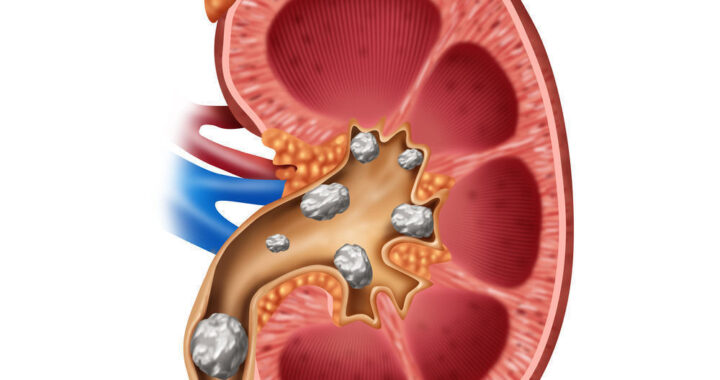

“CERDIK” Menuju Hidup Sehat Tanpa Penyakit Tidak Menular  Batu Ginjal dan Dampaknya: Kenali Sebelum Terlambat